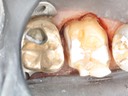

Wayne Chin #31 pre-op